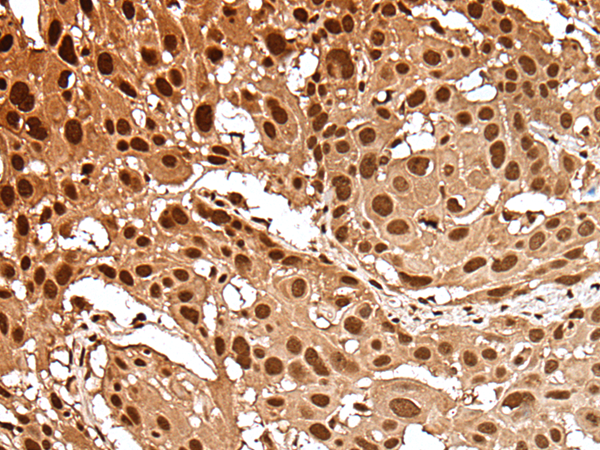

IHC positive control: |

Human esophagus cancer and human gastric cancer |